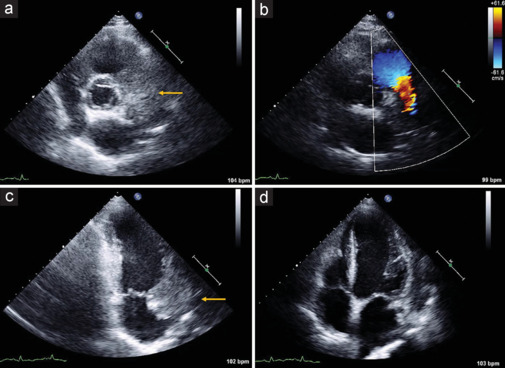

Cardiovascular disease and cancer constitute the most prevalent illnesses worldwide. Cancer patients show an increased risk of coronary artery disease not only due to shared cardiovascular risk factors, a pro-inflammatory and prothrombotic state induced by cancer itself, the cardiovascular toxicity of cancer therapy, or rarely, due to extrinsic compression of a coronary artery by the primary tumor or a metastatic lesion. Here, we present the case of a 59-year-old man with squamous cell carcinoma of the lung presented with asymptomatic diffuse ST segment depression and troponin T increase. Echocardiography revealed a large mass adjacent to the right atrium, atrioventricular groove, and basal segment of the anterior wall of the left ventricle, which the computed tomography scan showed to encase and probably compress the anterior descending coronary artery. Thus, the patient was diagnosed with acute coronary syndrome due to anterior descendent coronary artery compression by a neoplastic lung mass.